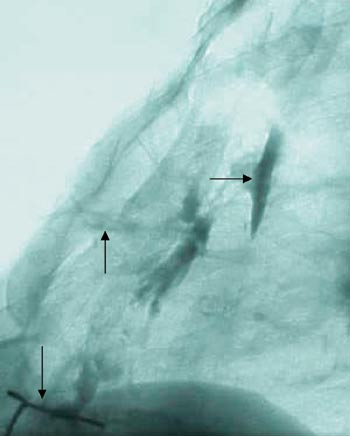

Denne behandlingen holdt ham symptomfri i sju måneder, da fikk han ny abscess over sternum. Abscessen ble incidert, og man fant en fistel. Fistulografi viste bred kommunikasjon inn mot karprotesen, men også ned mot gjenværende sternumsuturer (fig 1). De neste åtte månedene ble fistelen holdt åpen ved bruk av kvinnekateter med skyllinger (fig 2), men han fikk over en seksukersperiode tre nye septikemiepisoder, med gjentatt oppvekst av gule stafylokokker i blodkulturer. Han ble sykere for hver gang, og infeksjonen syntes å være helt ute av kontroll. Vi valgte derfor å forsterke suppresjonsbehandlingen ved å doble dosen trimetoprim-sulfametoksazol til 2 tabletter × 2, legge til fucidin 500 mg × 3, og fortsette med dikloksacillin i uendret dosering 500 mg × 3. Med denne behandlingen har pasienten vært symptomfri med normal CRP og senkning de siste 25 måneder.

Diagnosen er vanskelig, og hos vår pasient ble den endelig først etter at fistulografi viste kontrast inn til protesen (fig 1). Gjentatte torakale computertomografiundersøkelser viste ingen forandringer fra funnene gjort umiddelbart postoperativt, og verken torakal magnetresonansundersøkelse eller transøsofageal ekkokardiografiundersøkelse var til nytte. Leukocyttscintigrafi viste imidlertid oppladning av radioaktivt merkede leukocytter rundt aortaroten og skjerpet mistanken om proteseinfeksjon. Denne undersøkelsen rapporteres å være positiv i kun 50 % av tilfellene (10). Infeksjon oppstår i de fleste tilfeller i forbindelse med selve innsettingen av protesen (11), men proteseinfeksjon fra tilstøtende infeksjonsfokus eller etter bakteriemi er like sannsynlig hos vår pasient. Pasienten fikk alvorlig septikemi med gule stafylokokker bare fire dager etter innsetting av protesen og således før denne var epitelialiseret. Sternumløsning 14 dager etter sternotomien tydet på hissig osteomyelittisk prosess.